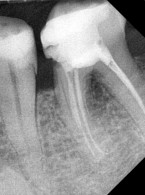

Zgłosiła się do mnie 60-letnia pacjentka z nieszczelną i nieestetyczną koroną protetyczną osadzoną na zębie siecznym szczęki. Pacjentka poinformowała, iż ząb był poddany przed laty zabiegowi resekcji. Wykonane zdjęcie potwierdziło wcześniej wykonaną apikotomię oraz obecność niewielkich zmian zapalnych w tkankach okołowierzchołkowych. W kanale stwierdzono dobrze kontrastujący się ćwiek (prawdopodobnie srebrny); w części koronowej kanału był widoczny krótki indywidualny wkład koronowo korzeniowy. Co mogę zasugerować pacjentce? Jakie są możliwości leczenia?